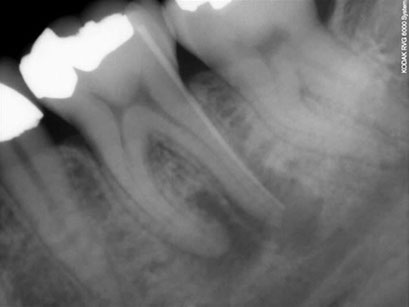

Il contenuto necrotico, infetto, del canale radicolare va a contaminare la zona circostante l’apice della radice,  determinando un Ascesso  o, altrimenti, una condizione d’infiammazione cronica,  detta Granuloma.

All'esame radiografico, sia l'Ascesso che il Granuloma sono rappresentati da  un'area di ridotta densità ossea, visibile come un'areola scura in prossimità dell'apice radicolare.